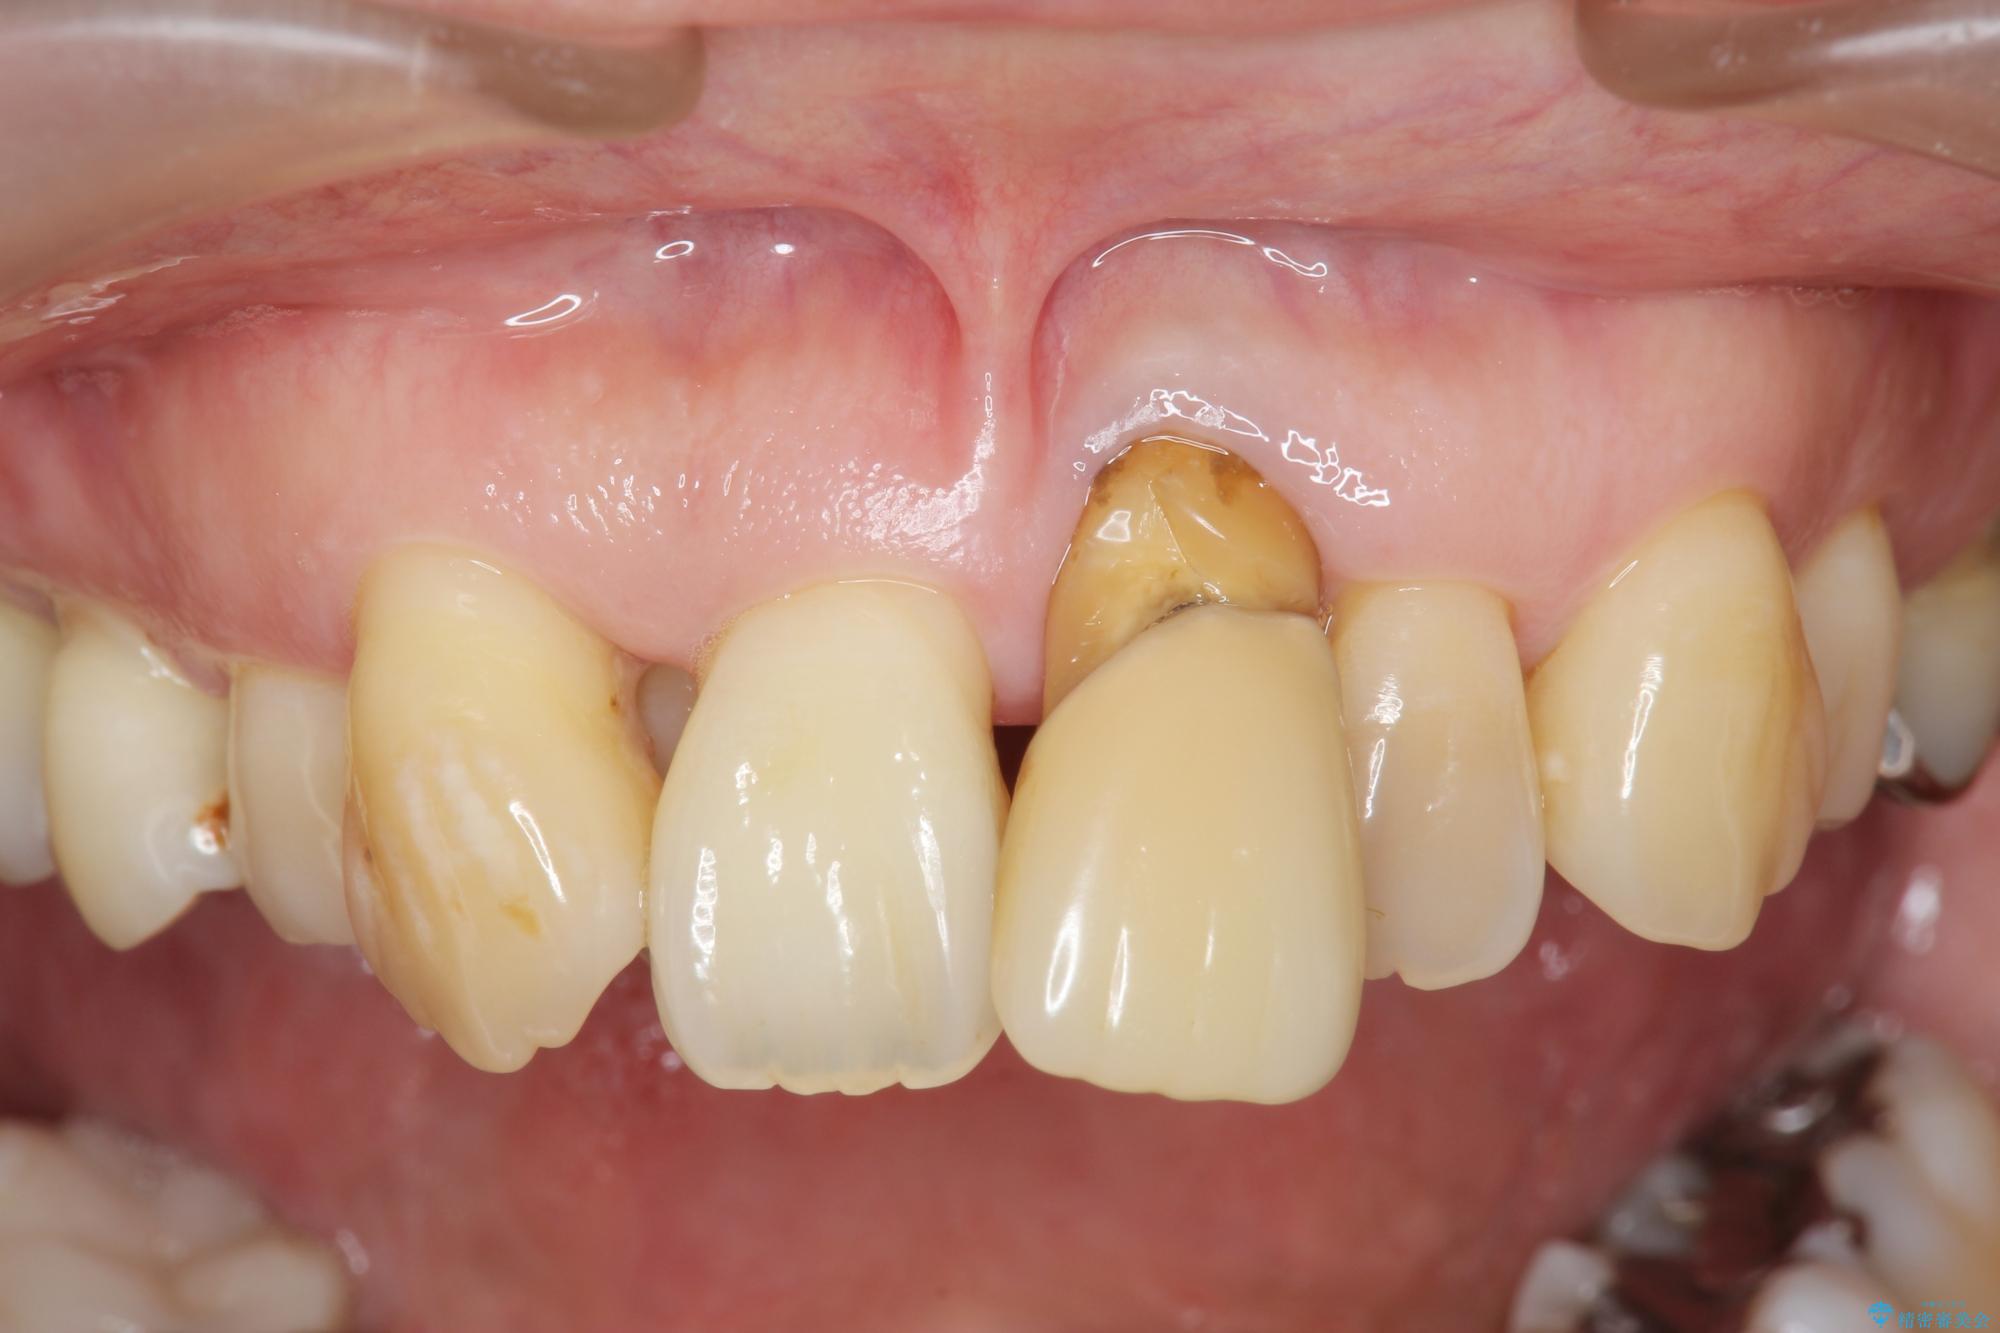

治療中

歯の総合的なマネージメントを行う包括的歯科治療の実践[ 歯周病・矯正・セラミック補綴 ] 治療中画像 歯の総合的なマネージメントを行う包括的歯科治療の実践[ 歯周病・矯正・セラミック補綴 ] 治療中画像 歯の総合的なマネージメントを行う包括的歯科治療の実践[ 歯周病・矯正・セラミック補綴 ] 治療中画像 歯の総合的なマネージメントを行う包括的歯科治療の実践[ 歯周病・矯正・セラミック補綴 ] 治療中画像 歯の総合的なマネージメントを行う包括的歯科治療の実践[ 歯周病・矯正・セラミック補綴 ] 治療中画像 歯の総合的なマネージメントを行う包括的歯科治療の実践[ 歯周病・矯正・セラミック補綴 ] 治療中画像 歯の総合的なマネージメントを行う包括的歯科治療の実践[ 歯周病・矯正・セラミック補綴 ] 治療中画像 歯の総合的なマネージメントを行う包括的歯科治療の実践[ 歯周病・矯正・セラミック補綴 ] 治療中画像 歯の総合的なマネージメントを行う包括的歯科治療の実践[ 歯周病・矯正・セラミック補綴 ] 治療中画像 歯の総合的なマネージメントを行う包括的歯科治療の実践[ 歯周病・矯正・セラミック補綴 ] 治療中画像 歯の総合的なマネージメントを行う包括的歯科治療の実践[ 歯周病・矯正・セラミック補綴 ] 治療中画像

まず、保存の難しい歯を抜去したのち矯正治療を行い歯並びの改善、歯周ポケットを除去したことで安定した歯周環境、咬合関係を作り出すことができました。

矯正治療を事前に行ったことで全ての歯の神経を温存しセラミックブリッジを装着することができました。